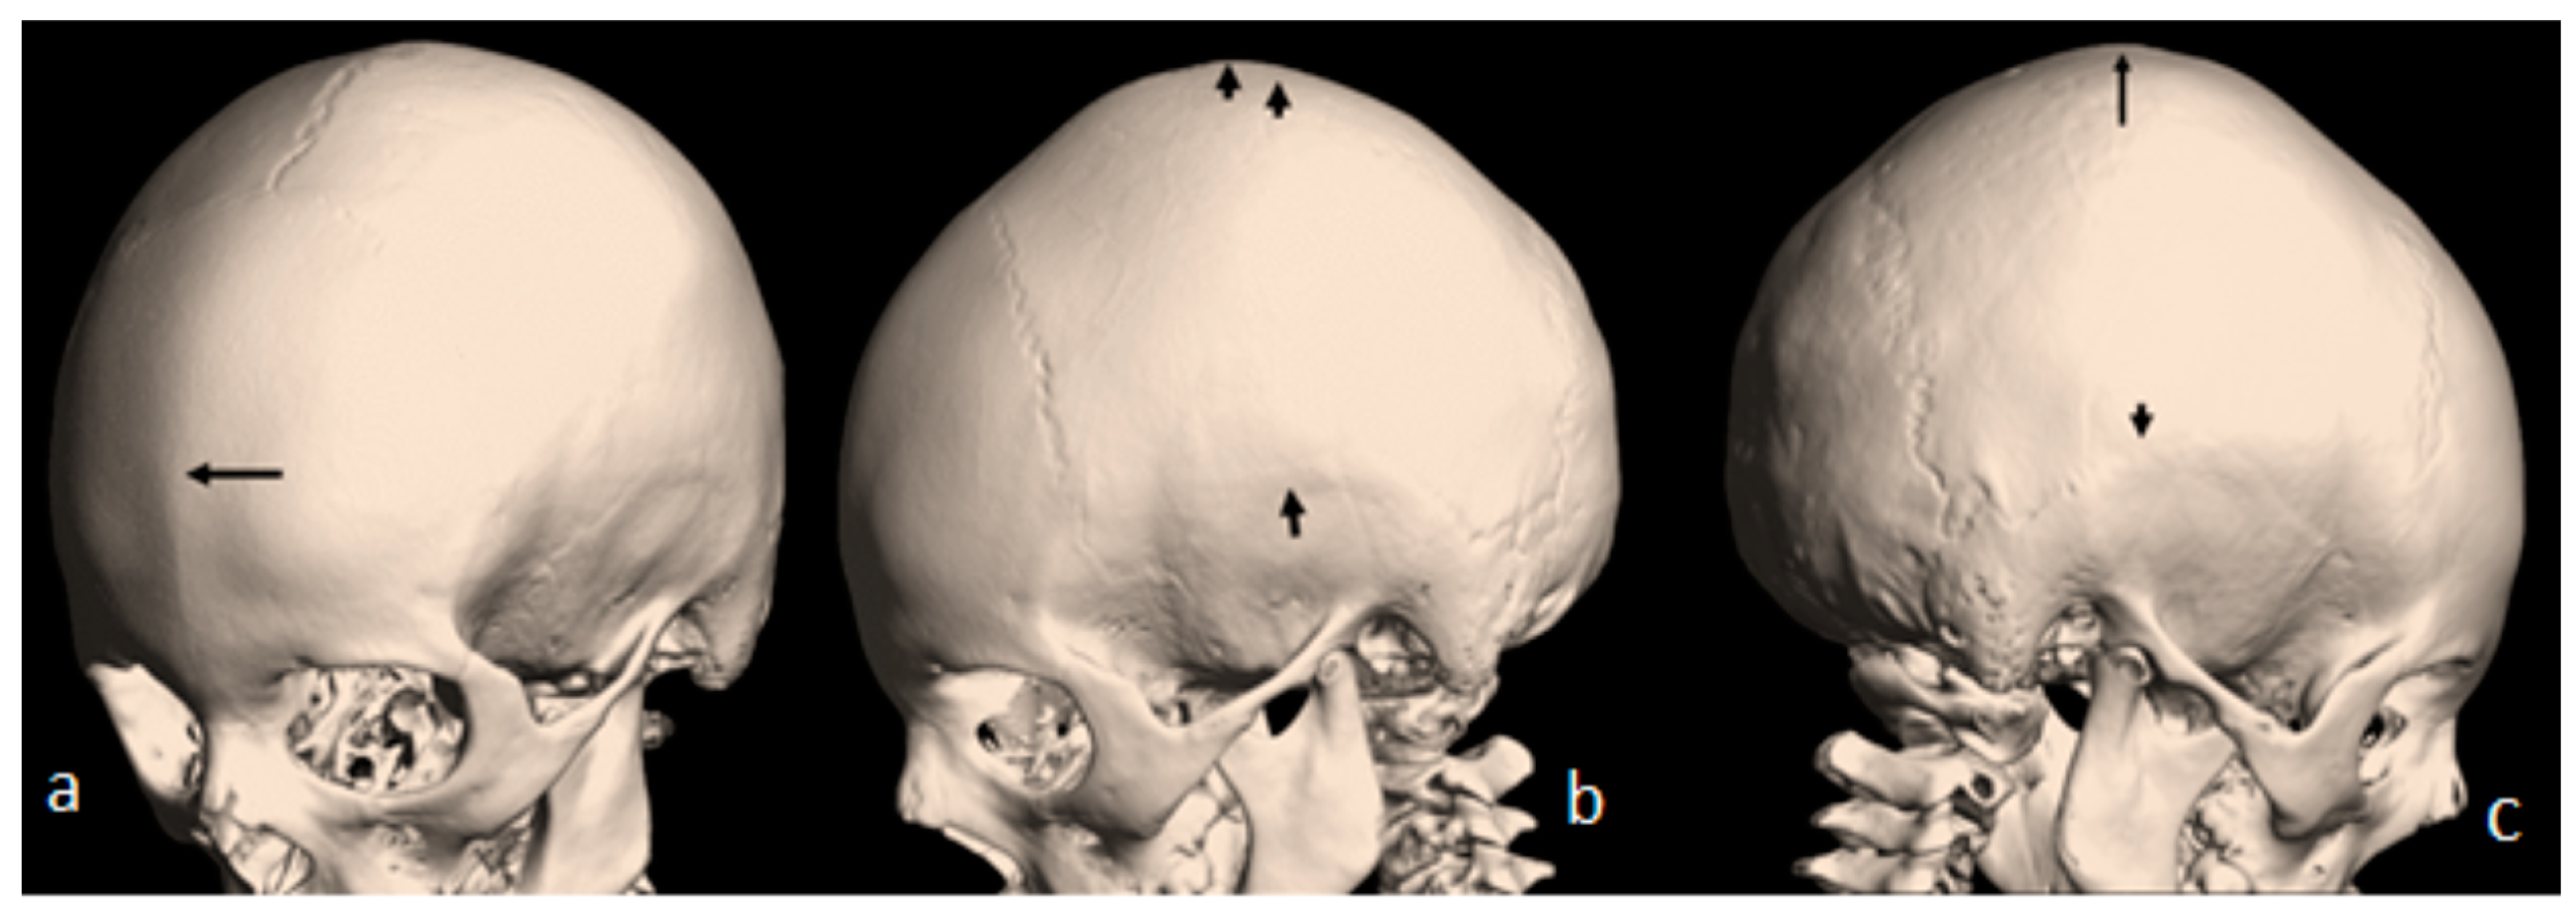

A 10-year-old boy received the diagnosis of West syndrome at the age of 3 and was referred to our department because of torticollis. Clinical examination showed a growth deficiency (10th percentile). Craniofacial asymmetry was a noticeable clinical feature. Examining the skull, we noticed asymmetrical massive bony ridges over the lambdoid sutures, with apparent but asymmetrical bulging of the occiput. The asymmetry was marked over the left portion of the left lambdoid, causing a bigger cranial compartment of the left over the right side of the occiput. A 3D axial reformatted CT scan of the 10-year-old boy illustrated the asymmetry of the posterior cranial bones along the lambdoid sutures Figure 3a). Interestingly, his 28-year-old mother has been a client at the department of spine surgery since she was 14. A 3D reconstruction CT scan of the mother showed a noticeable bony ridge extending from the metopic suture upwards to involve the sagittal suture (red arrow heads). The black arrow showed a well-demarcated boney ridge over the squamosal suture (Figure 3b). A 3D reconstruction CT scan of the skull and spine showed the thick bony ridge of the metopic and the anterior sagittal as well as bilateral involvement of the squamosal, causing apparent anterior narrowing of the craniofacial contour (blue arrow). Note the thoraco-lumbar scoliosis (Figure 3c).

Figure 3. (a) A 3D axial reformatted CT scan of the 10-year-old boy illustrated the asymmetry of the posterior cranial bones along the lambdoid sutures; (b) The black arrow shows a well-demarcated boney ridge over the squamosal suture. (c) A 3D reconstruction CT scan of the skull and spine of the mother note the thoraco-lumbar scoliosis.